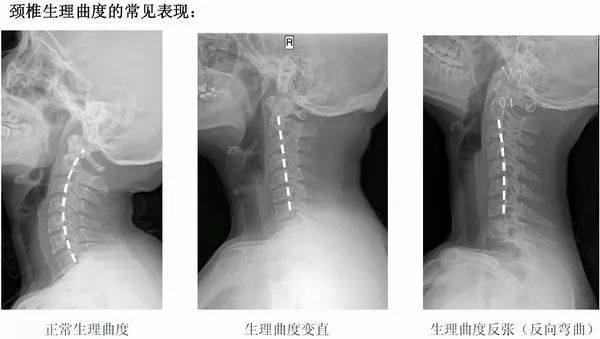

枕头的高度应以个人身材体格为标准,原则是,睡在枕上要能保持颈椎的正常曲线,不会使颈部扭曲。枕头以软硬度适中、稍有弹性为好。枕头太硬,头颈与枕接触的相对压力增大,会引起头部不适;枕头太软,则难以维持正常高度,使头颈部得不到一定支持而疲劳。